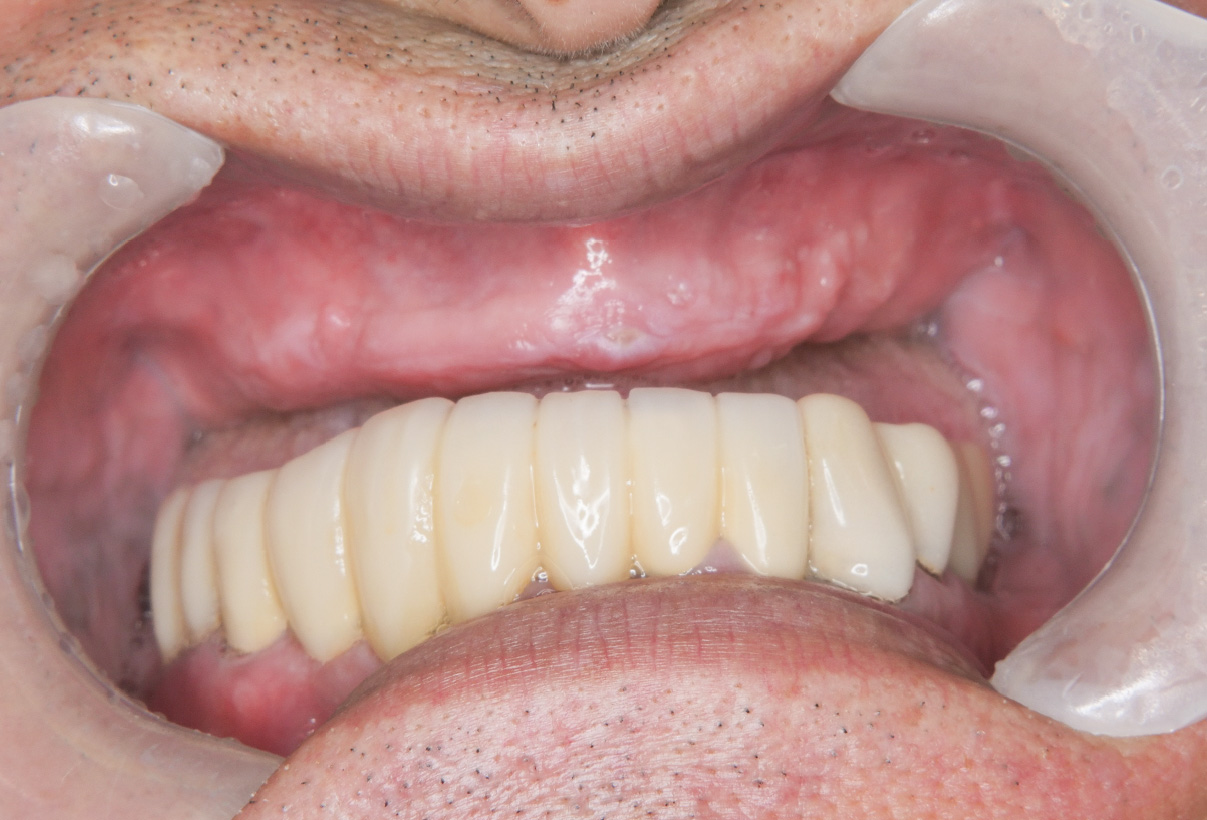

症例その3オールオン4

• Before

• After

咀嚼、審美障害。歯周病でグラグラな歯を全部抜歯してオールオン4で治療した症例。